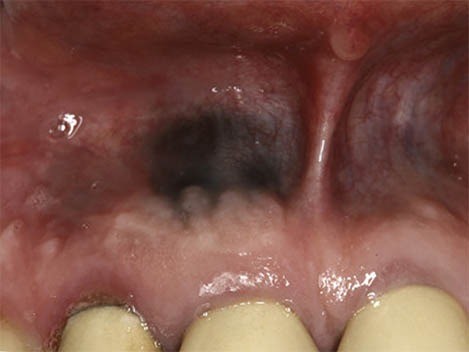

What Causes a Dark Spot on Gums?

Amalgam Tattoo

An amalgam “tattoo” occurs when a silver filling is being placed and some of the metal filling material inadvertently becomes lodged in the gum tissue or cheek. It usually looks like a small, irregularly shaped dark blue discoloration. They may look strange when you brush your teeth, but these dots are perfectly harmless and require no treatment.